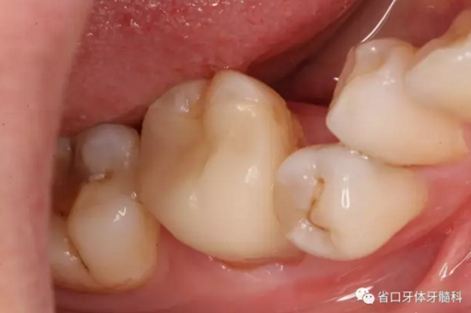

圖4 牙體預備后頰側(cè)觀